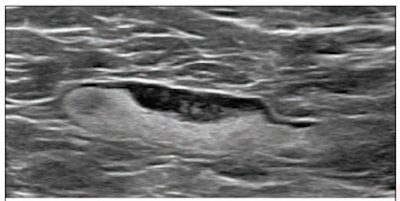

- A 38-year-old woman with family history of breast cancer evaluated for left breast pain with diagnostic mammography and ultrasound. Ultrasound showed a swollen lymph node; she underwent ultrasound-guided biopsy. She had received the first dose of the COVID-19 vaccine eight days before the initial mammogram and the second dose on the day of the biopsy.